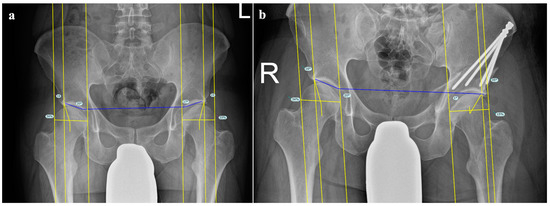

2.2. Preoperative Radiological Imaging

2.4. Postoperative Radiological Assessment